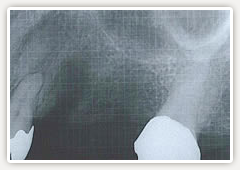

【術前】

ブリッジの土台の歯(手前)が悪くなり抜歯、再度ブリッジをして、これ以上自分の歯に負担をかけたくないそうです。

【術後】

ブリッジではなくインプラントを無くなった歯の代わりに追加しました。残った歯に対する負担も軽くなり、新たに手前の歯を削らずに済みました。